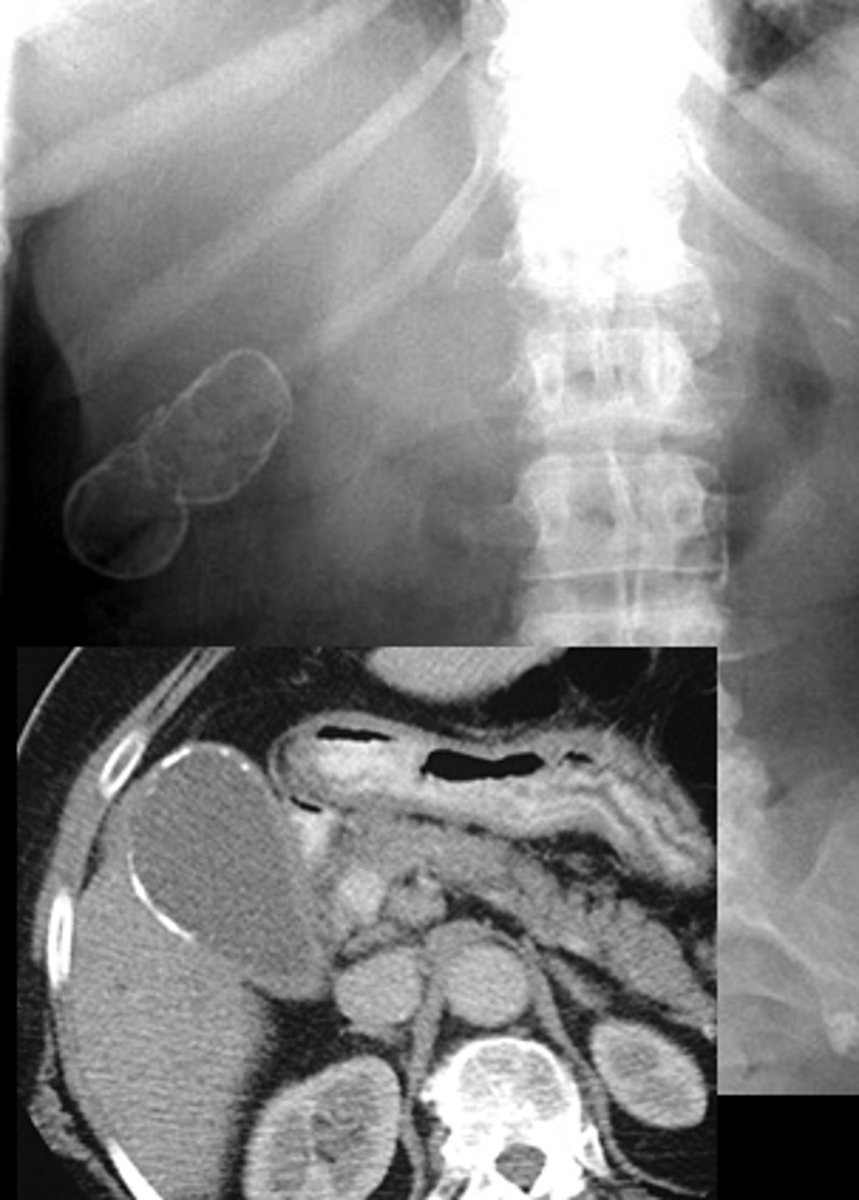

The development of palpable mass in the epigastrium 4 weeks after the onset of acute pancreatitis is highly suggestive of ___.

Pancreatic pseudocyst

- U/S

- only drain if it persists > 6 weeks, > 5 cm, or becomes secondarily infected